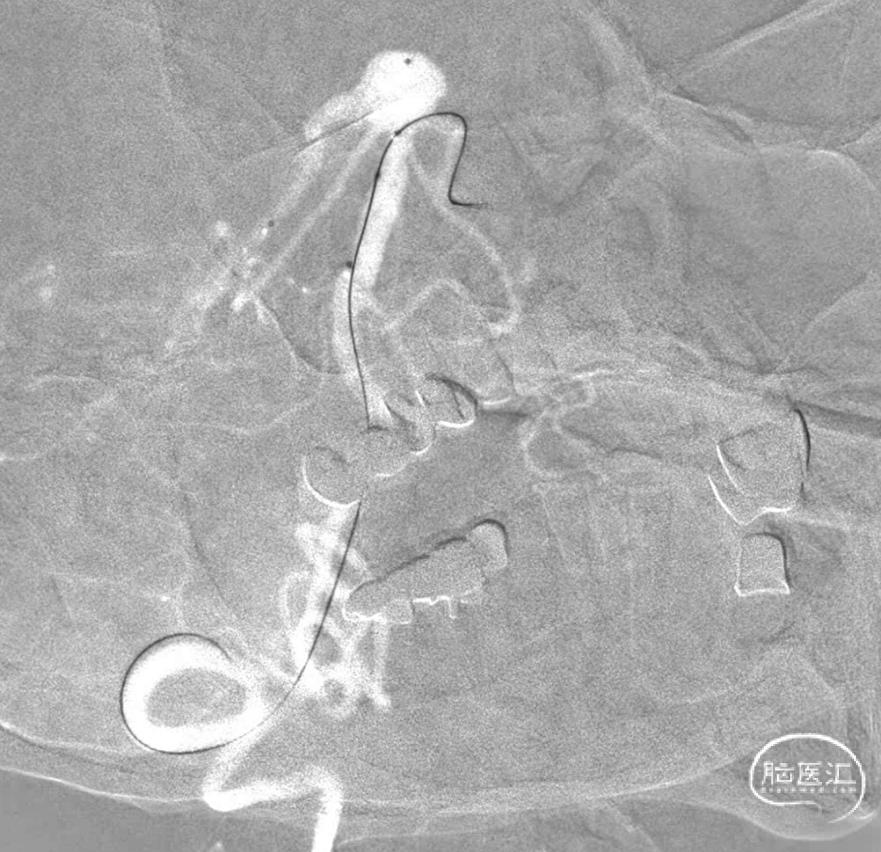

先填一个适当大小的圈,刚开始微导管头位置感觉差一些,借着弹簧圈比较软的优势,适当跟了一点微导管,感觉这个位置应该可以了,首先因为是大动脉瘤,通过简单的填塞很难把动脉瘤栓塞致密,因此一般选择分区填塞,因此计划是先把8,9点位置填的差不多后再回撤微导管,在回撤轨迹将弹簧圈依次填塞使其致密,但是凡事都是:身后有余忘缩手,眼前无路想回头。所以一切计划都存在变数。

第一个圈盘的还可以,直接支架辅助,一切都很顺利。微导管头的位置按原计划可行。

第一个圈填完,成型不错,弹簧圈微导管由于圈的张力作用,稍好低了一下头(红色标记),不过还好。

连续填了两枚圈,微导管头没变,但是开始左右摆圈。不好,根据以往经验,瘤顶偏右侧的空间要丢掉机会,如果再填一个圈,即将把动脉瘤颈部偏右侧大脑后动脉部分填致密,这样的话残留在瘤顶部的空白处可能填不上,因此直接采取下一方案。于是趁着瘤颈还有空间,将右侧支架导管撤下,将头塑型为指头或单弯,穿支架网孔到位。